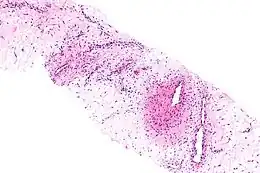

Coupe histologique d'un angiomyxome agressif (coloration à l'hématoxyline et à l'éosine)

L'angiomyxome agressif est une tumeur myxoïde impliquant les vaisseaux sanguins. Il peut affecter la vulve et d'autres parties du bassin.